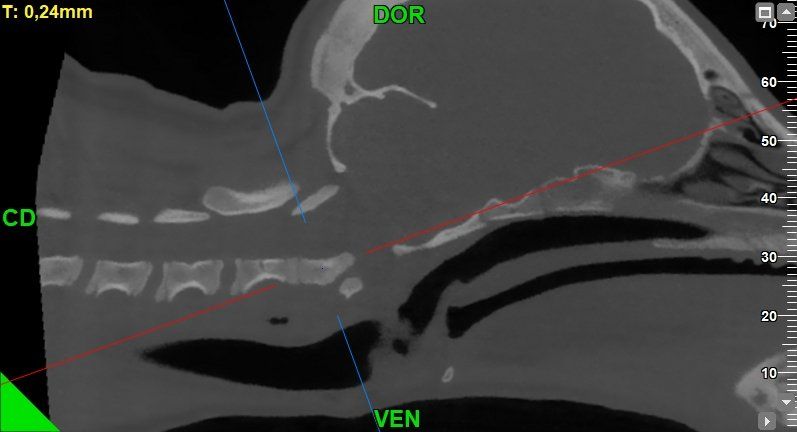

L’Ospedale Veterinario Città di Conegliano, in provincia di Treviso, mette a disposizione di tutti i propri pazienti un servizio di diagnostica radiologica avanzata, grazie al quale è possibile eseguire esami come la nuova TC di ultima generazione. Al servizio di radiologia digitale, infatti, oggi si associa la nuova TC con "cone beam technology".

L'esame TC consiste in uno studio completo che permette di visualizzare anche i più piccoli dettagli dell’anatomia del paziente. Si tratta di un esame rapido, indolore e del tutto non invasivo, e richiede solo la sedazione dell'animale.